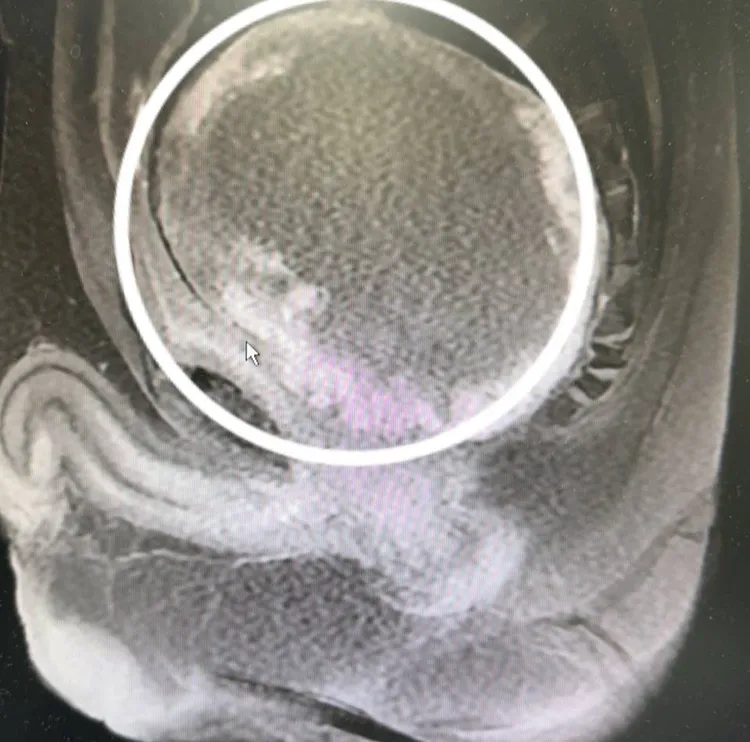

趙先生斷層檢查可見腫瘤位置及大小。阮綜合提供